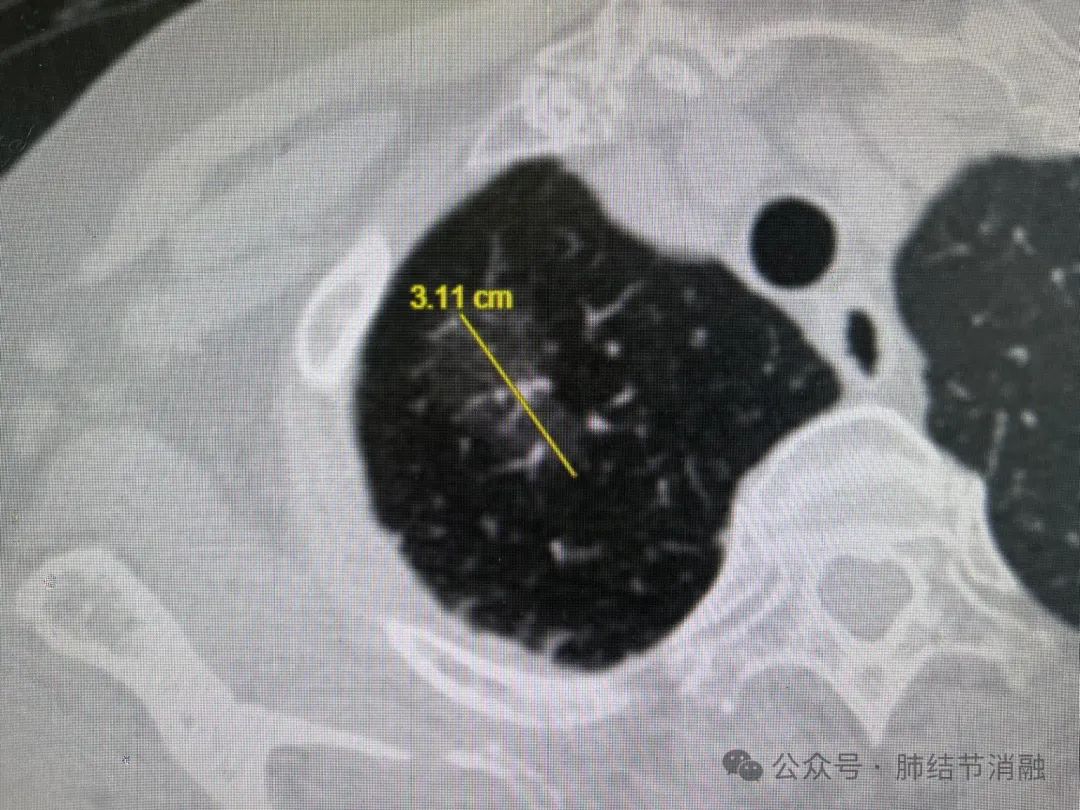

患者女性,86岁高龄,发现右肺尖磨玻璃结节6年余,逐渐长大,目前最大直径达3.1厘米,不耐受全麻手术,拟给予冷冻消融治疗。

患者术前CT图像